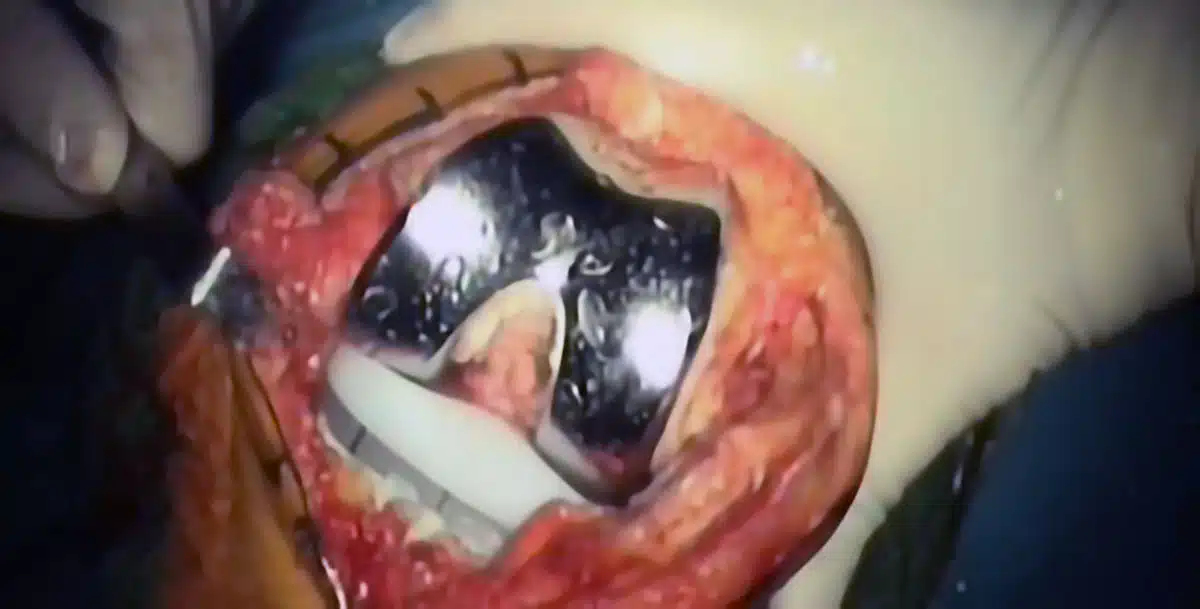

La qualità delle protesi reperibili sul mercato è ormai standardizzata e di livello. Ci sono modelli che prevedono un certo tipo di soluzioni chirurgica e ci sono modelli che ne prevedono altre. Nel campo delle protesi totali, per esempio, ci sono modelli che prevedono il sacrificio del crociato posteriore e ci sono modelli che prevedono invece la conservazione del legamento stesso. In termini di risultato questa è una differenza molto significativa. Conservando il crociato posteriore, la performance del ginocchio risulterà certamente migliore. Ci sono ulteriori differenze tra protesi e protesi ma rientrano in un ambito prettamente scientifico, forse più da addetti ai lavori e sulle quali non credo serva soffermarsi in questa sede. Ci sono poi le protesi monocompartimentali. Sono protesi che, a differenza delle totali, sostituiscono solo uno dei tre compartimenti del ginocchi, che sono il mediale, il laterale e il femoro-rotuleo. Nel 90% dei casi la protesi monocompartimentale è mediale. Nel 10% dei casi è laterale. La protesi monocompartimentale sottorotulea è molto rara. Questi tipi di protesi vanno a sostituire solo la parte danneggiata, lasciando inalterato, perché sano, il resto del ginocchio, e dunque l’impatto chirurgico è più limitato di quello che abbiamo con l’impianto di una protesi totale. Inoltre il complesso legamentoso viene completamente risparmiato, per cui la biomeccanica articolare della protesi monocompartimentale è molto vicina a quella del ginocchio sano, mentre nella protesi totale è fondamentalmente diversa: quindi la performance del risultato della protesi monocompartimetale risulta maggiore, che nella protesi totale. C’è dunque un recupero decisamente più rapido e più soddisfacente per il paziente. Si può dire che, con la protesi monocompartimentale, il ginocchio torna a livelli di funzionalità quasi normali.

L’impatto chirurgico è certamente invasivo, più per la protesi totale che per quella monocompartimentale. Si è costretti ad eseguire dei tagli ossei ed in parte anche muscolari; si va a sacrificare almeno un legamento, qualche volta due nel caso delle protesi totali. È un intervento che presume un grossolano sanguinamento, anche se ormai, grazie all’emostasi da compressione, al lavoro del chirurgo e al contributo dei farmaci, la perdita di sangue è divenuta più limitata. Ovviamente, nel caso della protesi monocompartimentale l’impatto sarà meno significativo, anche se -ribadiamolo- l’intervento è e rimane comunque invasivo.